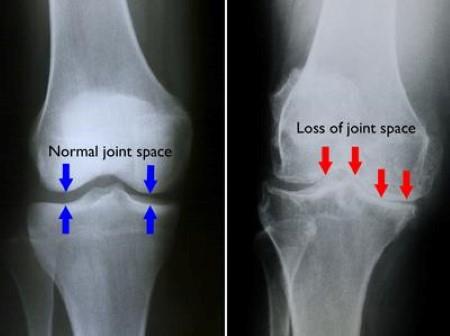

Osteoarthritis: Degenerative joint disease characterized by loss of cartilage and joint space.

Injuries: Meniscal tears, cruciate ligament ruptures, collateral ligament injuries.

Joint replacement: May be necessary if the hip or knee joint is beyond repair.